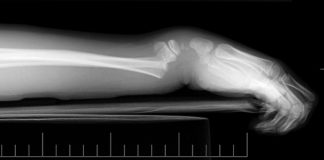

- Examen ostéo-articulaire à la recherche de déformations, fractures ou luxations.

Le médecin légiste peut demander une radiographie du corps avant de commencer l’autopsie s’il le juge nécessaire. Cet examen est notamment indispensable pour :

- Identifier et localiser des fractures, des cals osseux (reformation de l’os après une fracture) ou des liaisons osseuses spécifiques permettant d’évaluer leur ancienneté (ce sont des éléments très souvent utilisés dans les cas de violences et maltraitances)

- Rechercher et localiser un projectile balistique (Est-ce que le projectile s’est fragmenté ? S’est-il logé dans un os ? Quelle est la trajectoire du projectile dans le corps (balistique lésionnelle) ?)

- Identifier une personne (Est-ce que la personne est porteuse d’une prothèse ? d’une broche ? d’un pace maker ? Peut-on déterminer approximativement l’âge de la victime au regard de ses os ? Est-ce que la personne porte un appareil orthodontique ? etc.)